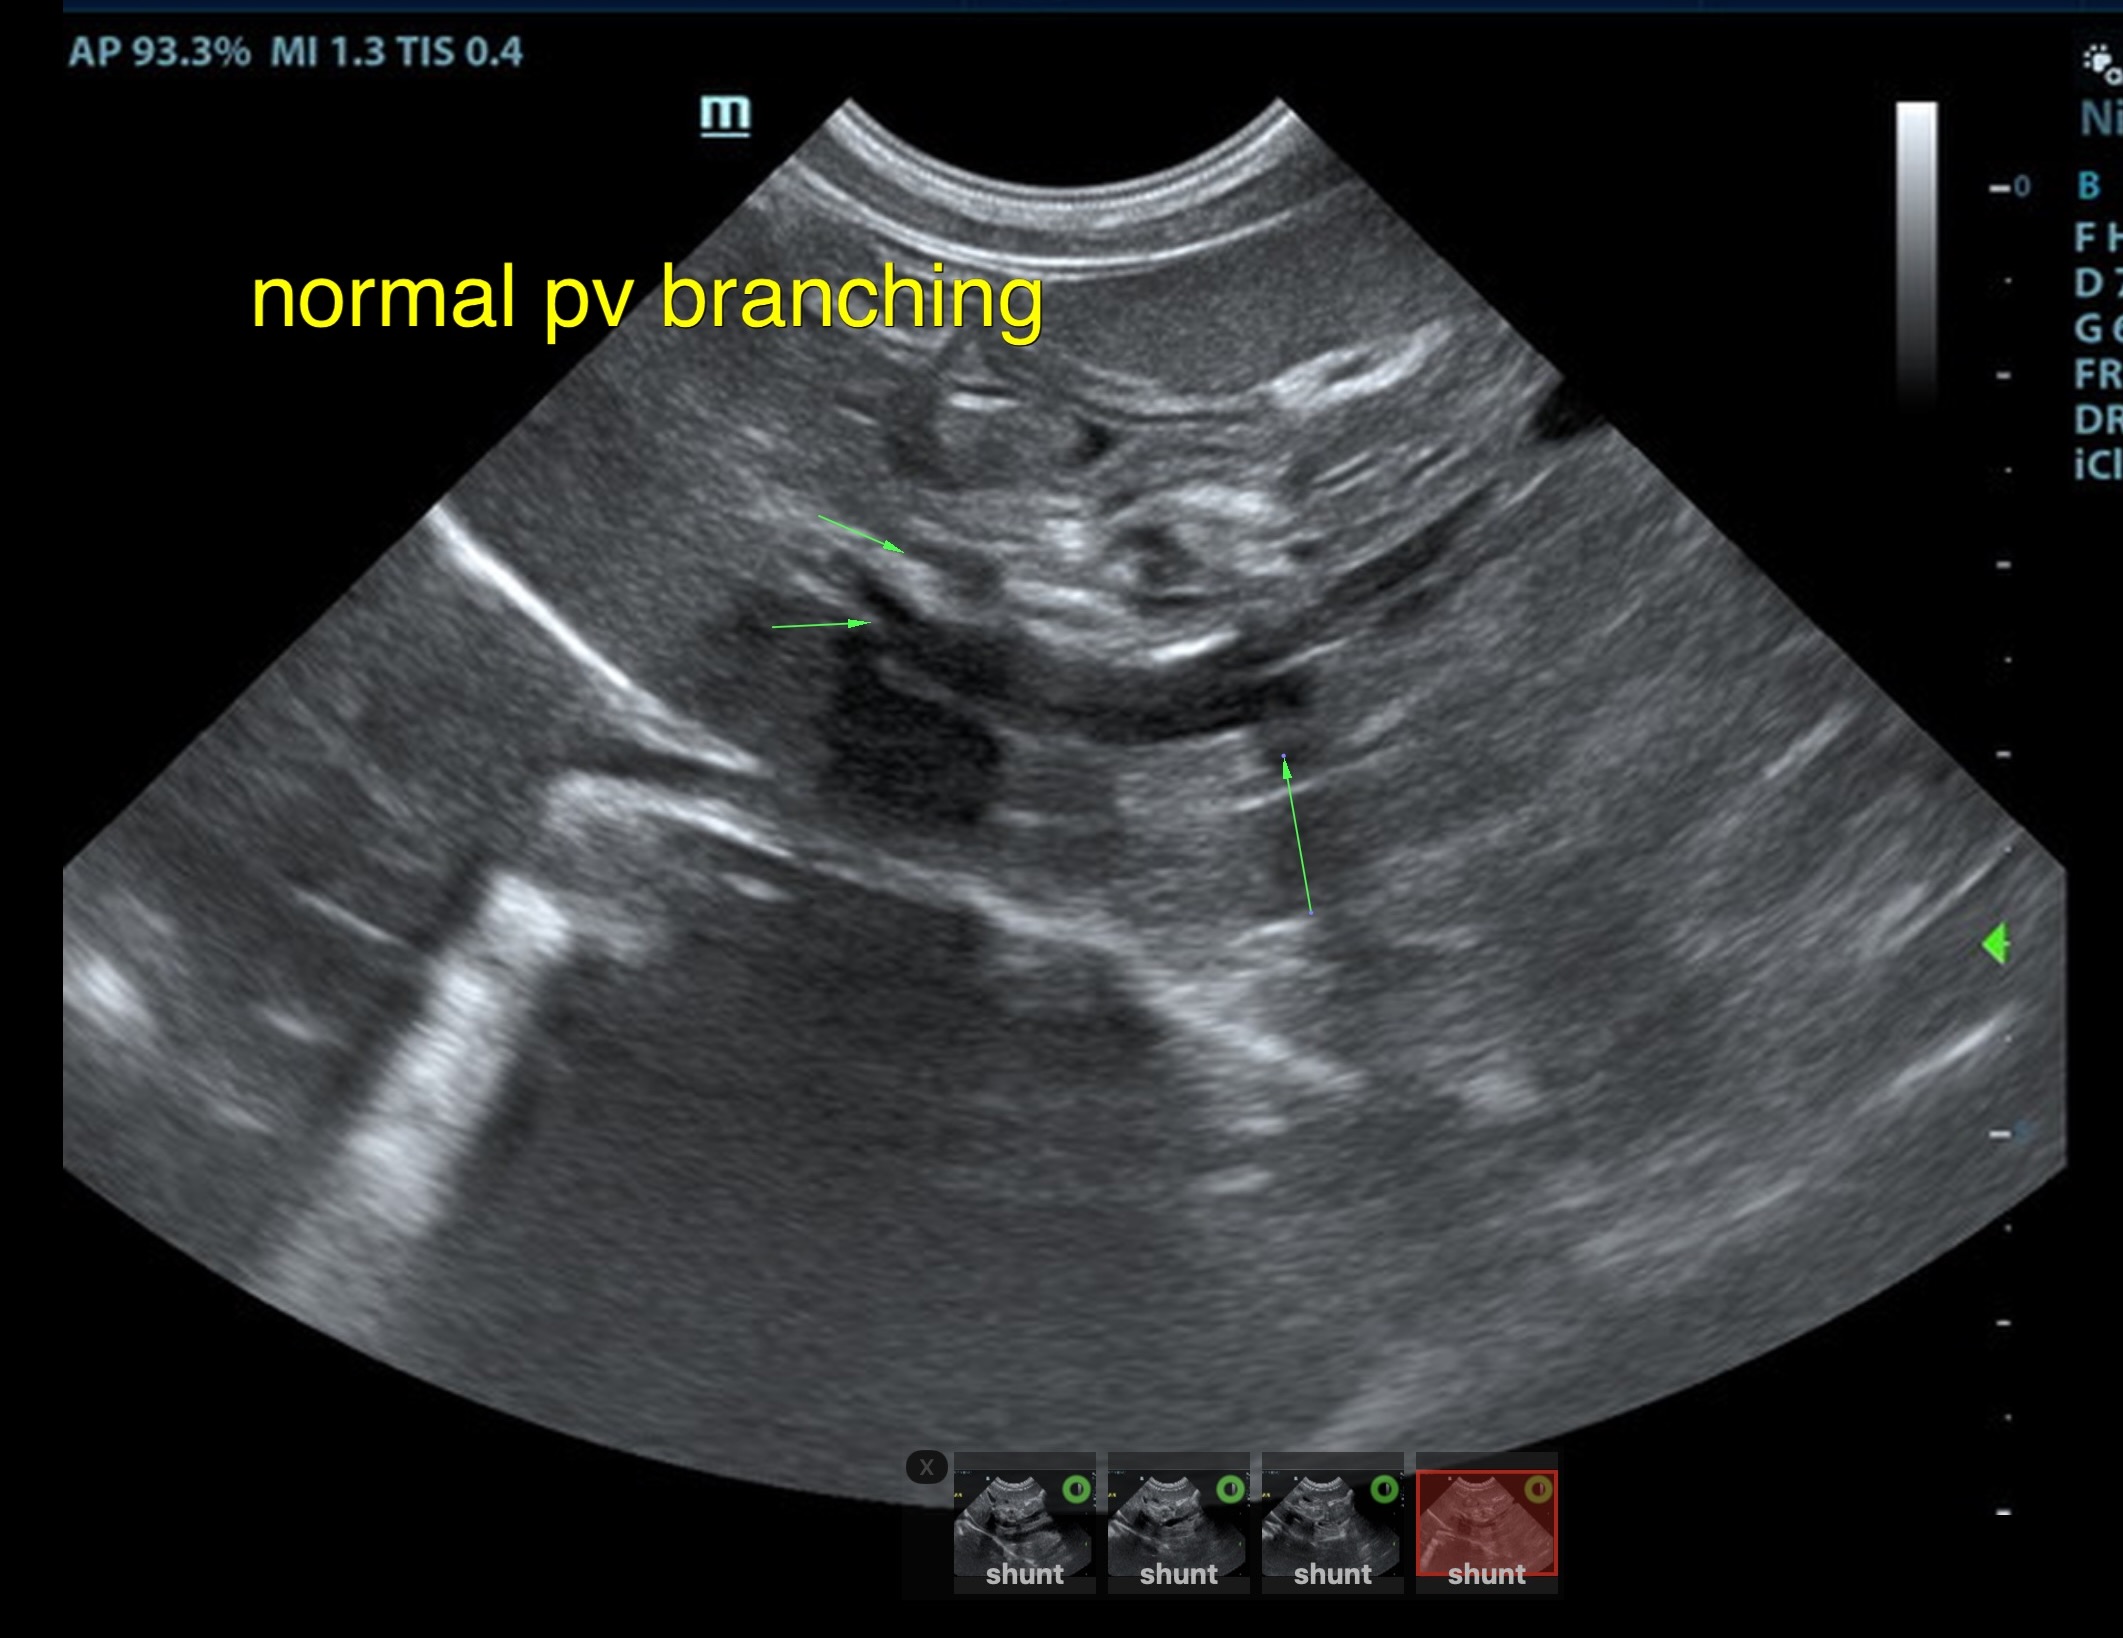

The liver was subnormal in size, yet the portal vein and vena cava ratio was 1:1. The portal veins were subnormal in size and measured 0.34 cm. The vena cava was enlarged and measured 0.34 cm. The vena cava was enlarged and measured 0.72 cm, aorta measured 0.4 cm. The branching of the portal vein appeared to be normal and of adequate volume. The portal vein and vena cava measured 0.5 cm each in the extrahepatic space. The splenic vein entry into the portal vein and gastroduodenal vein entry into the portal vein appear to be normal. There was one turbulent vessel in the region of the central branch of the portal vein, which may represent an intrahepatic shunt, but this could not be confirmed. The width of the shunt is approximately 0.76 cm. This is in position of central divisional shunt; however, right divisional origin cannot be completely ruled out. The gallbladder presented acceptably thin walls with primarily anechoic content. The cystic and common bile ducts were normal.